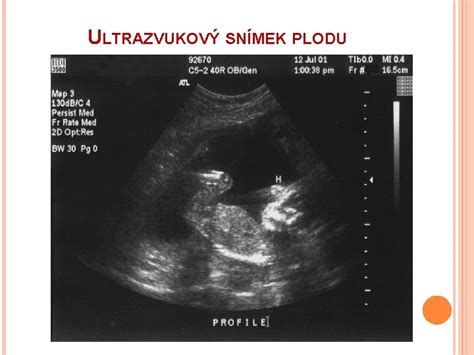

Počas tehotenstva lekári využívajú niekoľko kľúčových meraní na sledovanie rastu a vývoja plodu. Tieto merania sú často označované skratkami, ktoré môžu byť pre budúce mamičky mätúce. Pochopenie týchto skratiek však pomáha lepšie porozumieť informáciám z ultrazvukových vyšetrení:

- CRL (Crown-Rump Length): Temeno-kostrčová vzdialenosť. Toto je najčastejšie meranie v raných štádiách tehotenstva, zvyčajne od 6. do 20. týždňa. Meria sa od vrcholu hlavičky po kostrč plodu.

- BPD (Biparietal Diameter): Priečny priemer hlavičky. Meria sa vzdialenosť medzi spánkovými kosťami hlavičky plodu. Je to dôležitý parameter na určenie gestačného veku, najmä medzi 14. a 24. týždňom tehotenstva.

- HC (Head Circumference): Obvod hlavičky. Ďalší parameter, ktorý sa používa na odhad gestačného veku plodu.

- FL (Femur Length): Dĺžka stehennej kosti. Toto meranie je jedným z najpresnejších parametrov na určenie gestačného veku, najmä v období od 10. do 25. týždňa tehotenstva.

- AC (Abdominal Circumference): Obvod brucha. Hoci nie je najspoľahlivejším ukazovateľom gestačného veku, AC je kľúčový pre odhad hmotnosti plodu (EFW - Estimated Fetal Weight).

- EFW (Estimated Fetal Weight): Odhadovaná hmotnosť plodu. Vypočítava sa na základe rôznych biometrických meraní, najmä AC a FL, a poskytuje informáciu o aktuálnej váhe bábätka.